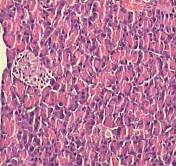

The morphometric examination of the normal pancreatic tissue sections showed that the islets are of normal size and have intact Beta cells. STZ-treated pancreatic specimens showed shrunk islets with degenerated Beta cells and peripheral lymphocytic infiltrate. Sections of pancreatic tissue treated with Pio (10 mg/kg) showed small islets with decreased number of Beta cells than control. Sections of pancreatic tissue treated with MP (500 mg/kg) showed that the islets had decreased number of Beta cells. Sections of pancreatic tissue treated with Pio (10 mg/kg) in combination with MP (250 mg/kg) showed atrophic islets with few Beta cells (fig. 10), (table 1).

Fig. 10: Photomicrograph of Pio, MP and Pio+MP on liver in STZ-treated diabetic rats. STZ: streptozocin Pio: pioglitazone, MP: Monascus purpureus. [mean±SEM, n= 6] significant, * when compared to normal and @ P<0.05 when compared to control diabetic

A-Section in control liver tissue showing preserved hepatic architecture with normal hepatocytes (H and E, X100). B-Section in normal pancreatic tissue, the islets show intact Beta cells (H and E, X100). C-Normal pancreatic tissue section with overlapped binary image showing a mean islet area 1278.26 square micrometer. D-Section of liver tissue from STZ treated rat showing normal hepatic architecture with focal inflammatory cell infiltrates with focal hepatocytic degeneration (H and E, X100). E-STZ pancreatic tissue section, the islets show degenerated Beta cells with peripheral lymphocytic infiltrate (H and E, X100). F-Pancreatic sections from STZ treated rat with overlapped binary image showing a mean islet area 785.42 square micrometer. J-Section of liver tissue from Pio treated rat showing moderate degeneration of hepatocytes with mild cellular infiltrate (H and E, X100). K-Pio treated pancreatic tissue section showed that the islets have few Beta cells (H and E, X100). L-Pancreatic sections from Pio treated rat with mean islet area 549.28 square micrometer. M-Section of liver tissue from Stat treated rat showing moderate hepatic infiltration by inflammatory cells (H and E, X100). N-Stat treated pancreatic tissue section showed that the islets had decreased number of Beta cells (H and E, X100). O-Pancreatic sections from Stat treated rat with mean islet area 724.11 square micrometer. P-Section of liver tissue from PS treated rat showing focal degeneration of hepatocytes (H and E, X100). Q-PS treated pancreatic tissue section; the islets show decreased number of Beta cells with peripheral inflammatory cellular infiltrate (H and E, X100). R-Pancreatic sections from PS treated rat with mean islet area 659.89 square micrometer.